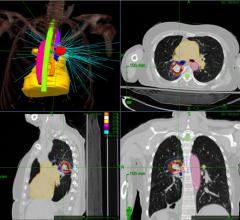

This is Reflexion’s X1 LINAC radiotherapy system on display at ASTRO 2021. It recently gained FDA clearance for standard ...